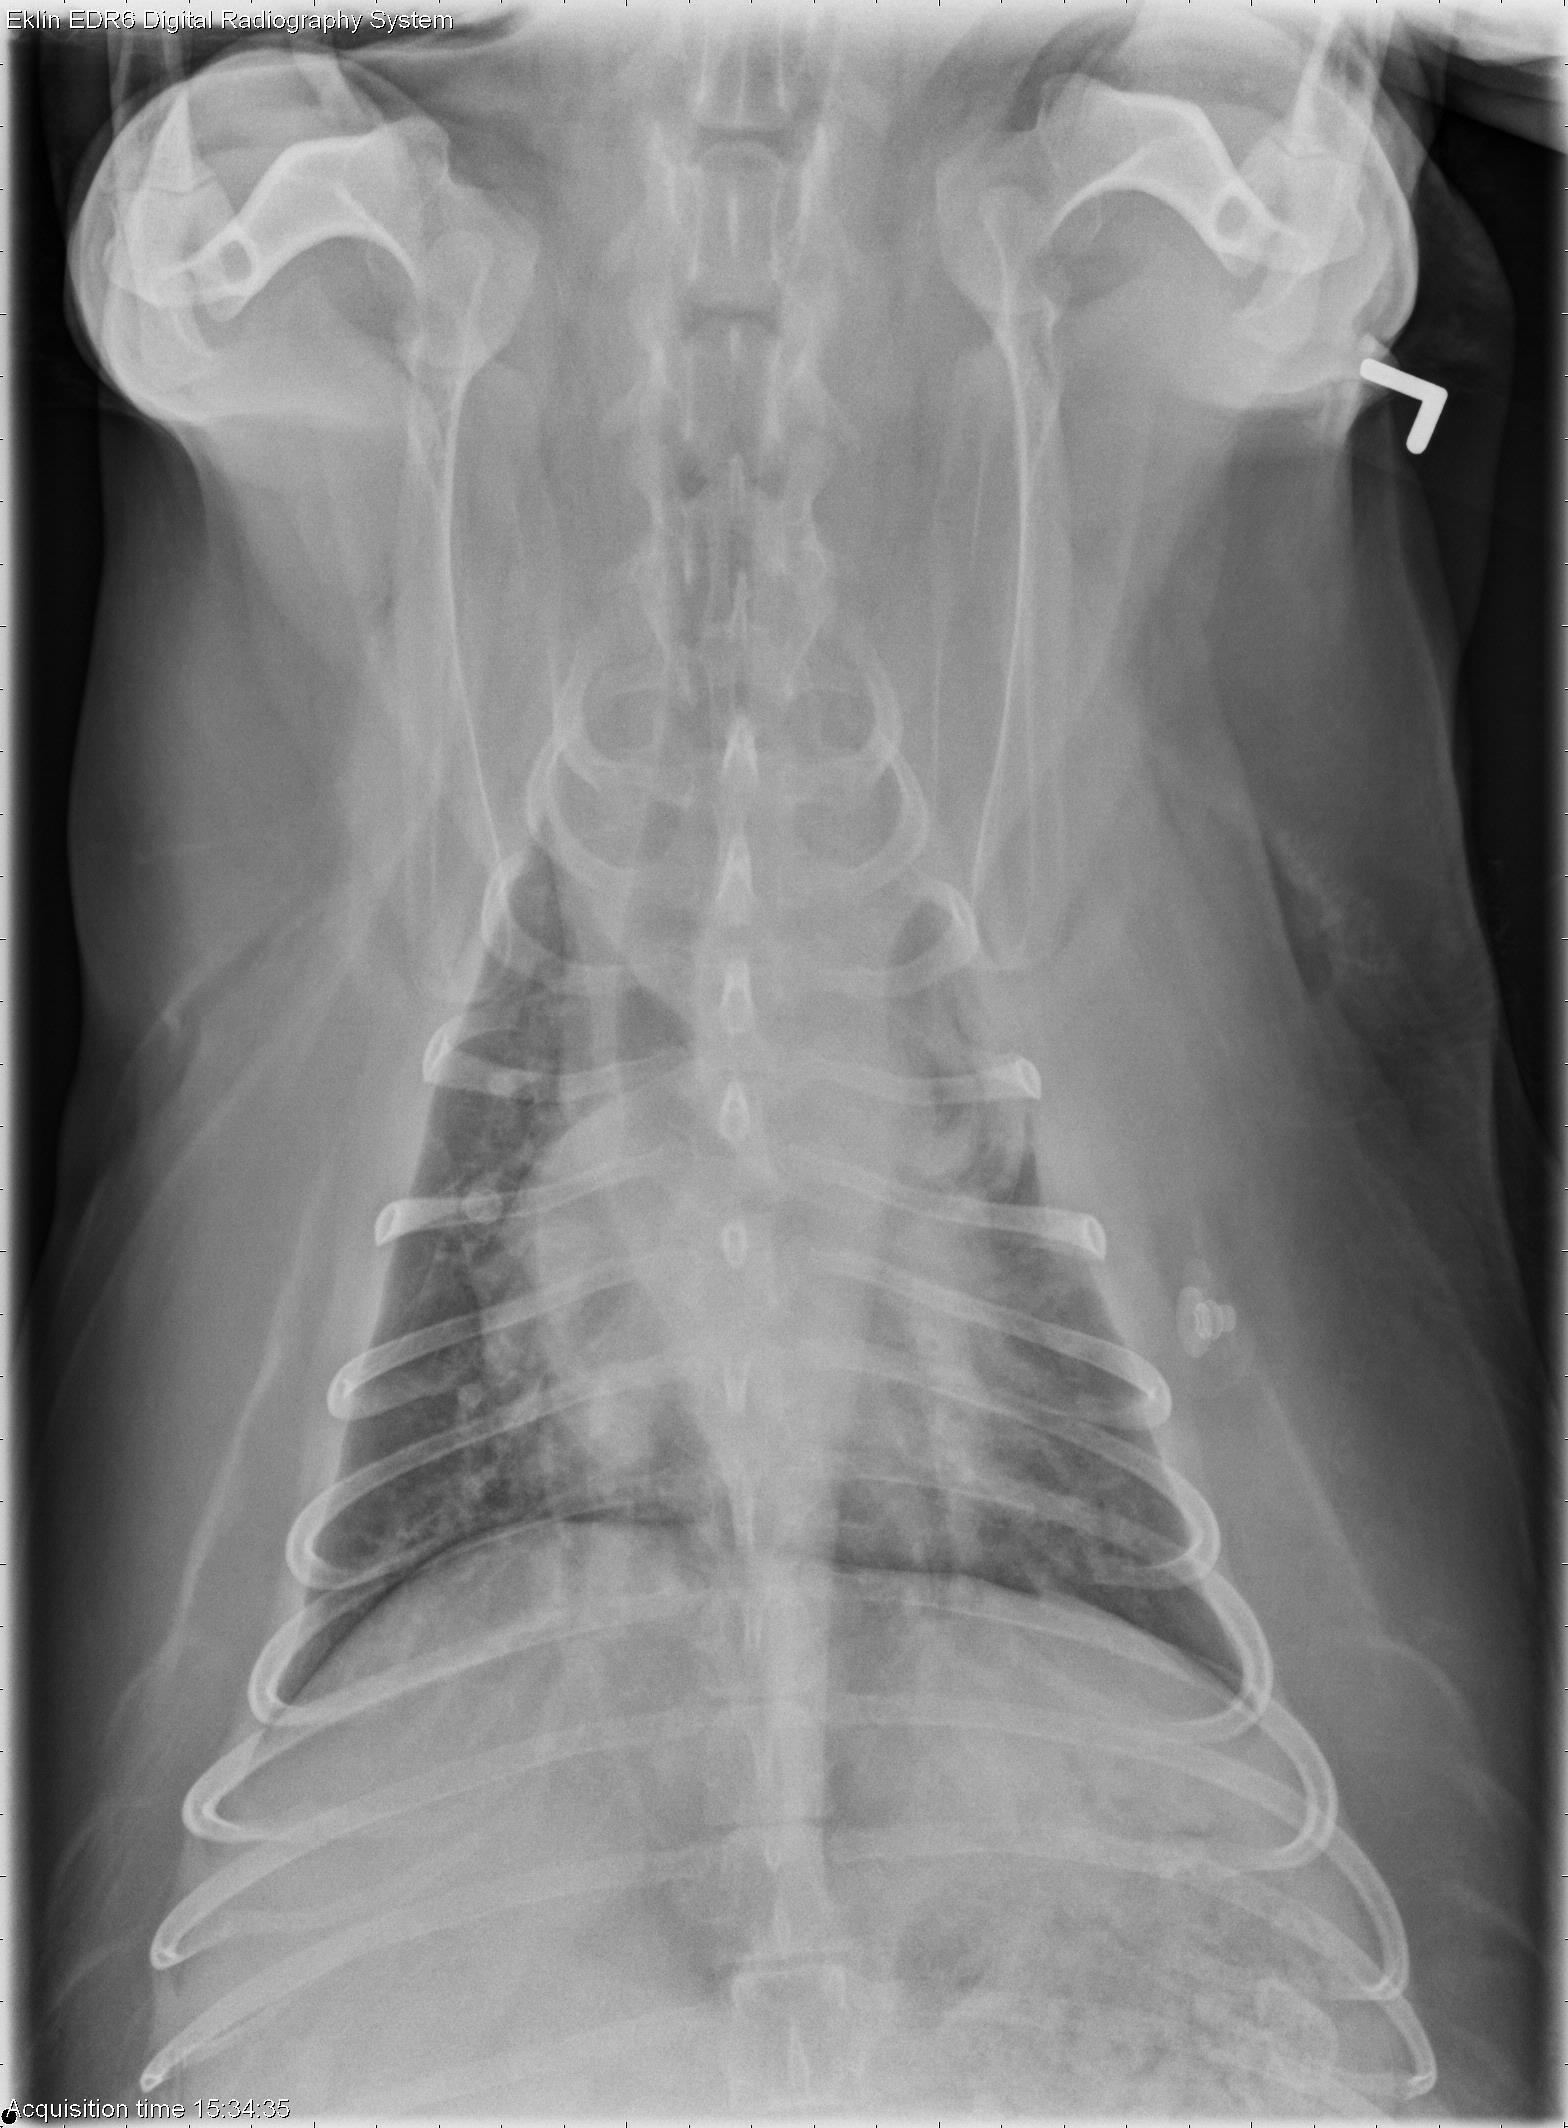

This week’s case is an 11-year-old male neutered Cocker Spaniel with bleeding tendencies. What are your findings?

VD Thorax

There is a patchy, diffuse interstitial to alveolar pattern throughout the lungs. There is a more focal alveolar pattern in the left cranial lung lobe which does not completely resolve between the dorsoventral and ventrodorsal projections. The cranial mediastinum appears widened. The heart is mildly enlarged, and the pulmonary vasculature is enlarged with some vessels tapering abruptly.

• Diffuse pulmonary changes -ARDS, pulmonary thromboembolism, hemorrhage, embolic infectious pneumonia

• Cardiomegaly – valvular disease, endocarditis

• Cranial mediastinum – fat, hemorrhage, mass

IMHA and ITP with secondary microvascular thrombosis and acute sepsis, resulting in embolic pneumonia and early ARDS.